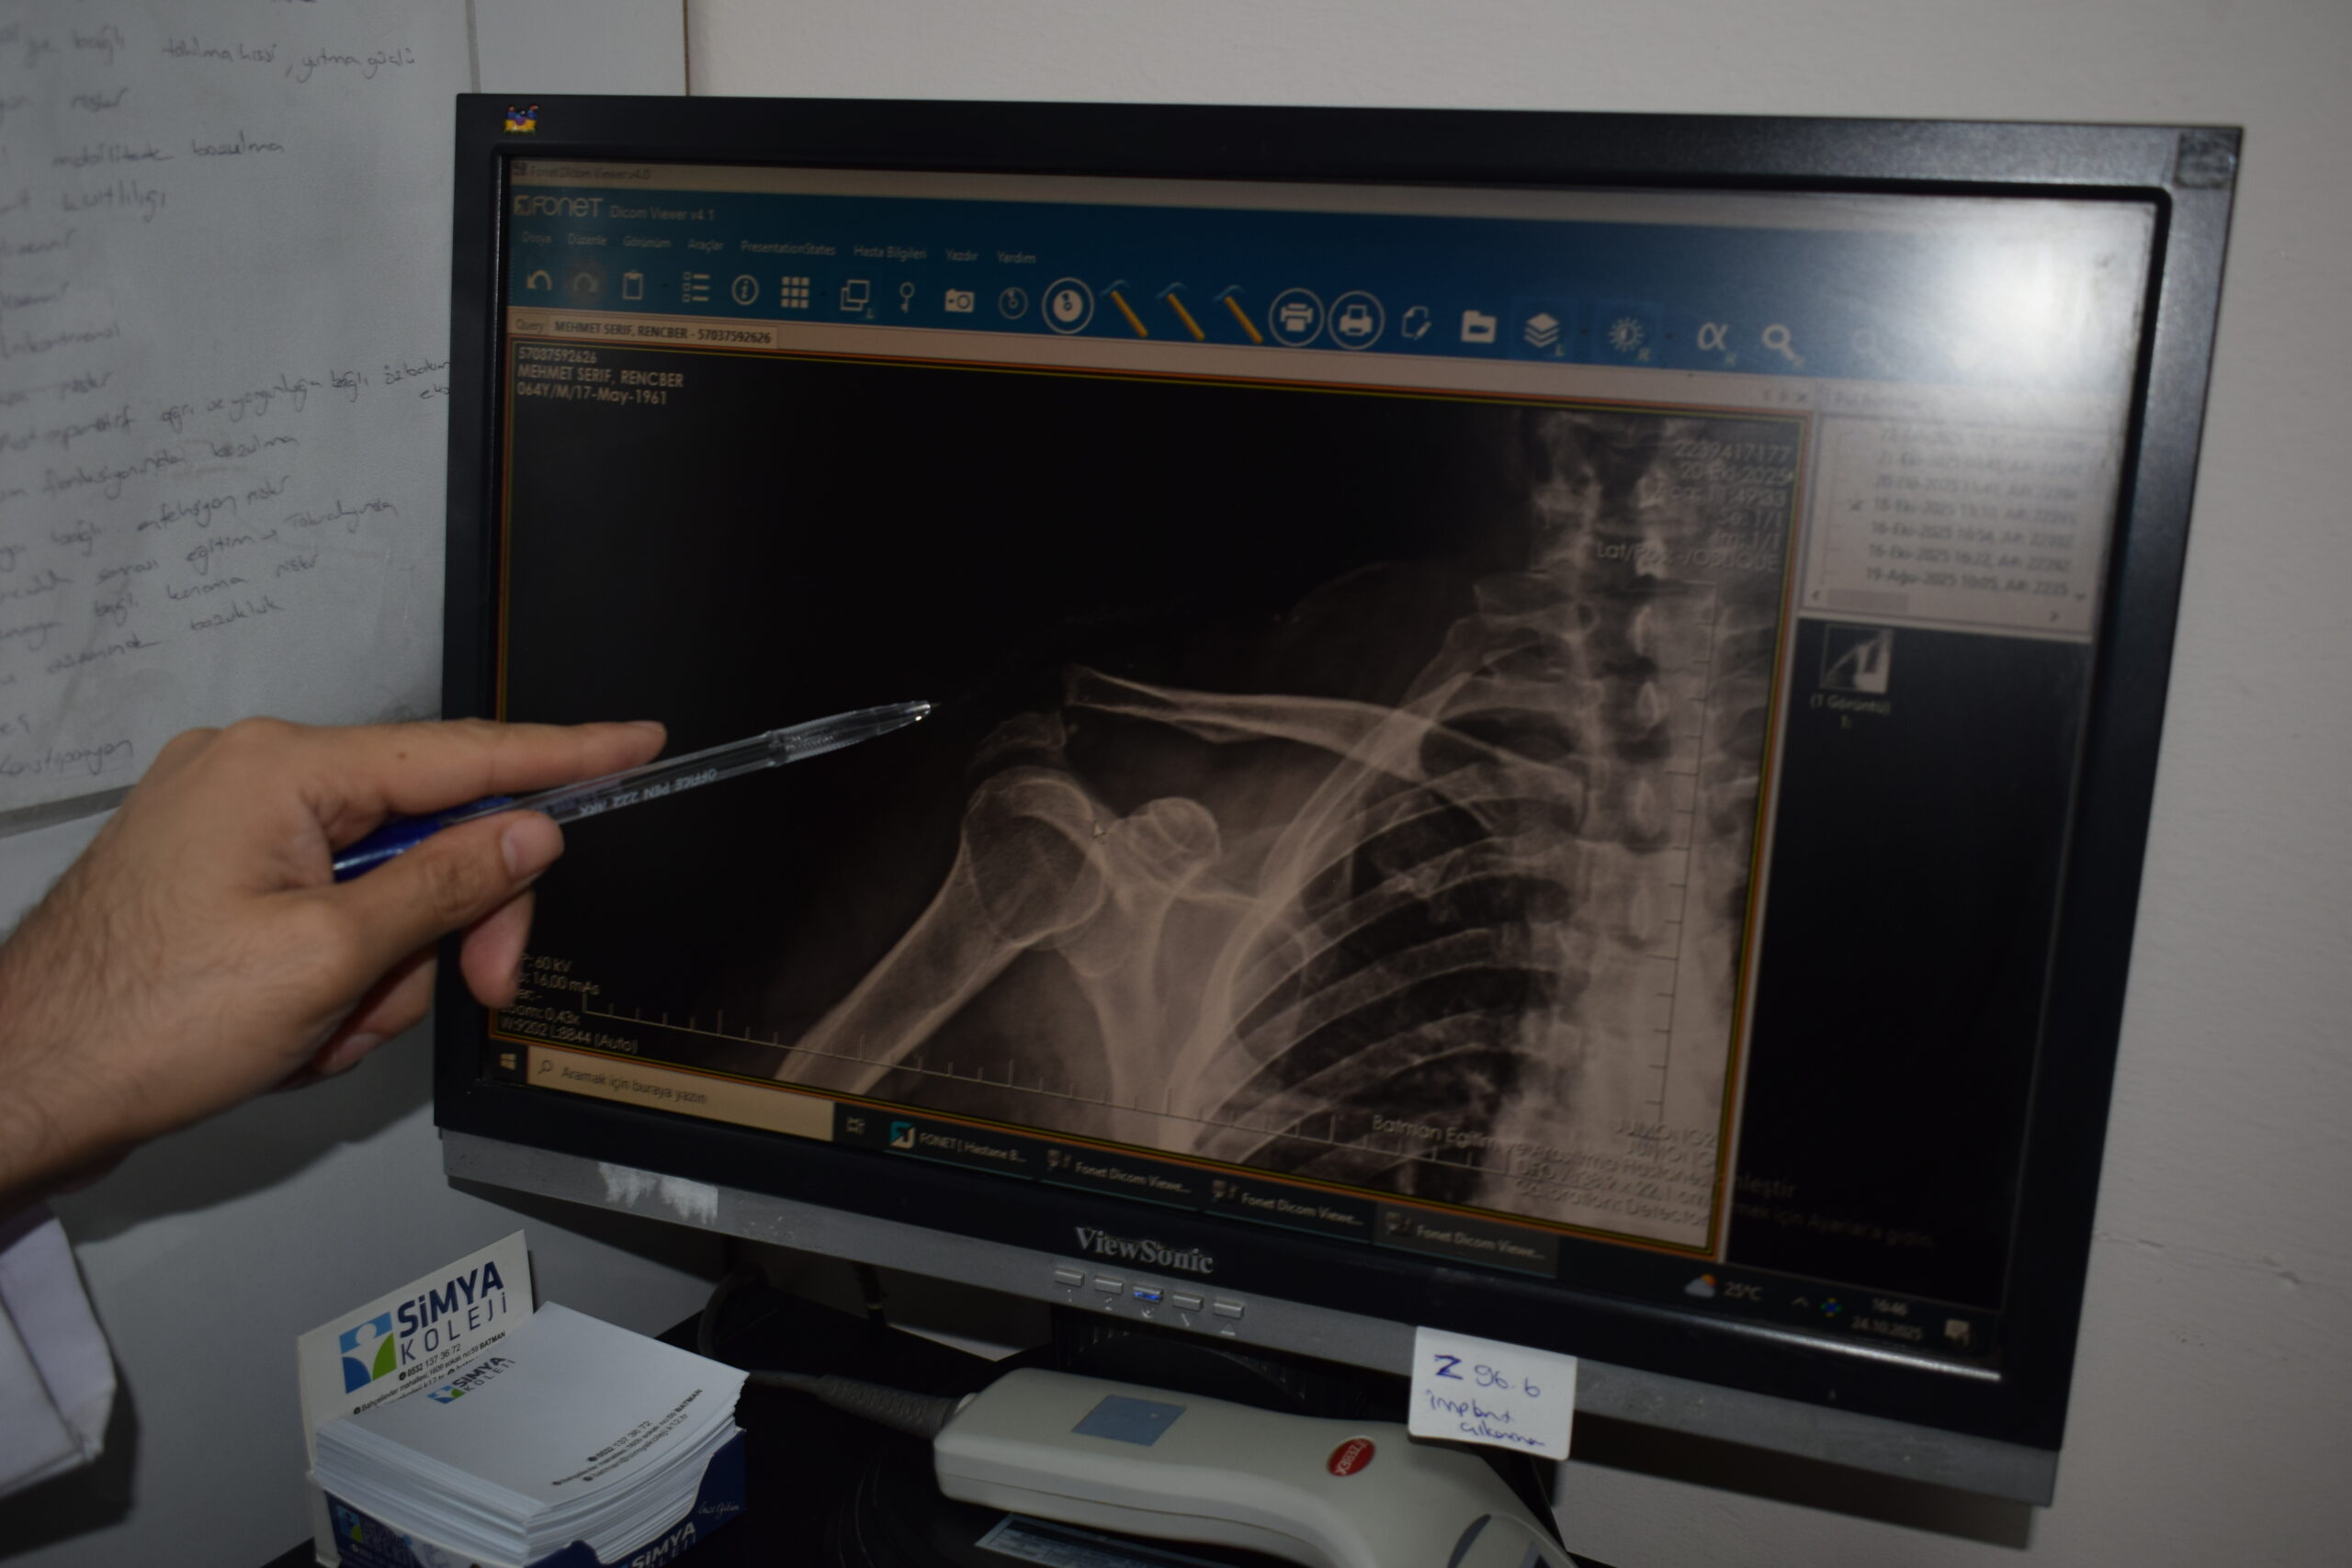

Ortopedi ve Travmatoloji Uzmanı Dr. Mehmet Yavuz Başer’in gerçekleştirdiği ameliyatta, Rençber’in omzuna kemik yapısıyla tam uyumlu, nadir kullanılan özel bir plak yerleştirildi.

Ameliyatın çok başarılı geçtiğini belirten Dr. Mehmet Yavuz Başer, “Genelde gençlere ameliyat önerilirken bu hastamıza yaşından dolayı bazı sıkıntılar olduğu söylenmiş. Biz kendisiyle konuştuk ve aktif birisi olduğu için ameliyat kararını daha uygun gördük. Ameliyatımız çok şükür güzel geçti. Nadir kullanılan bir plaktan kullandık, o da hastamıza tam olarak uydu” dedi.